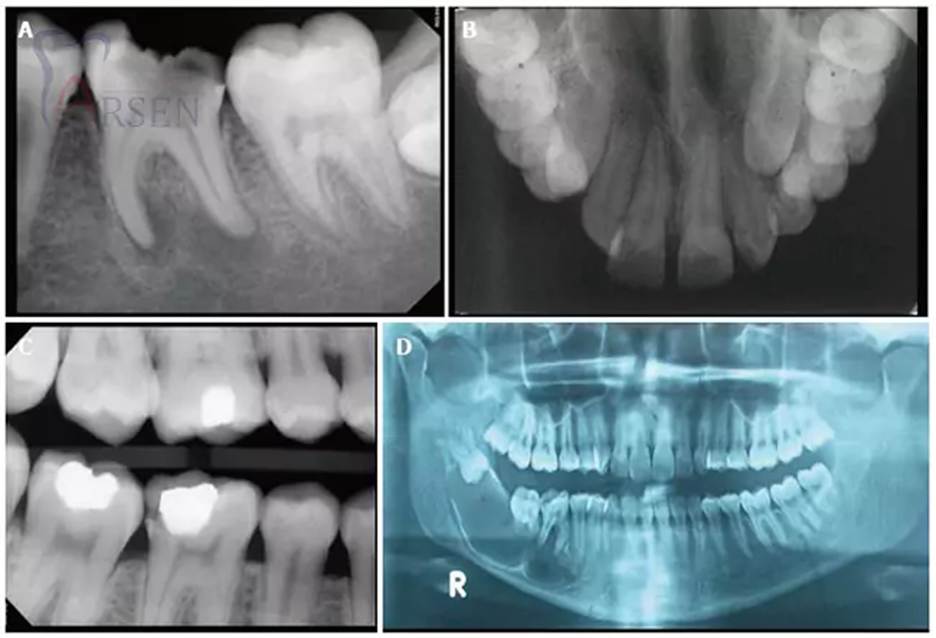

انواع روشهای رایج رادیوگرافی در دندانپزشکی

در حوزه دندانپزشکی ایران، روشهای مختلفی برای تصویربرداری از دندانها و ساختارهای دهانی استفاده میشود. این روشها به دو گروه داخل دهانی و خارج دهانی تقسیم میشوند که شامل:

داخل دهانی

رادیوگرافی بایت وینگ (Bitewing)

رادیوگرافی تک دندان (Periapical)

رادیوگرافی اکلوزال (Occlusal)

خارج دهانی

پانورامیک

سفالومتریک (Celphalometry)

توموگرافی (CBCT)

هر یک از روش های بالا بسته به نوع مشکل دندانی و نیاز بیمار بهطور خاص کاربرد دارند. در ادامه به معرفی رادیوگرافی پری اپیکال ساخت ایران میپردازیم.

نقش تصویربرداری در تشخیص بیماریهای دهان و دندان